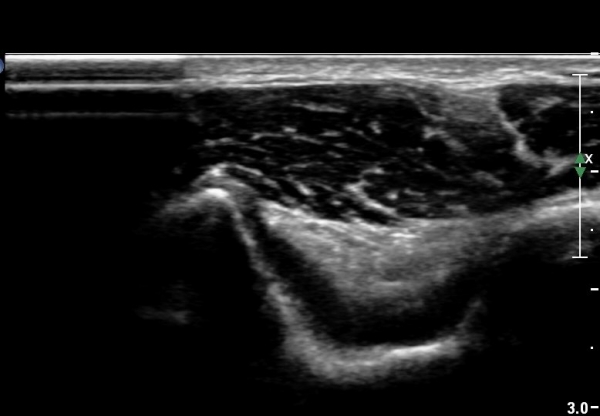

¿Ü»ó°ú Á¾´Ù¸é°Ë»ç¿¡¼­ ªÀº¼Õ¸ñ½ÅÀü°Ç ºÎÂøºÎ¿¡ ±¹¼ÒÀûÀÎ Àú¿¡ÄÚ º¯È­°¡ °üÂûµÊ(»çÁø 1, 2).